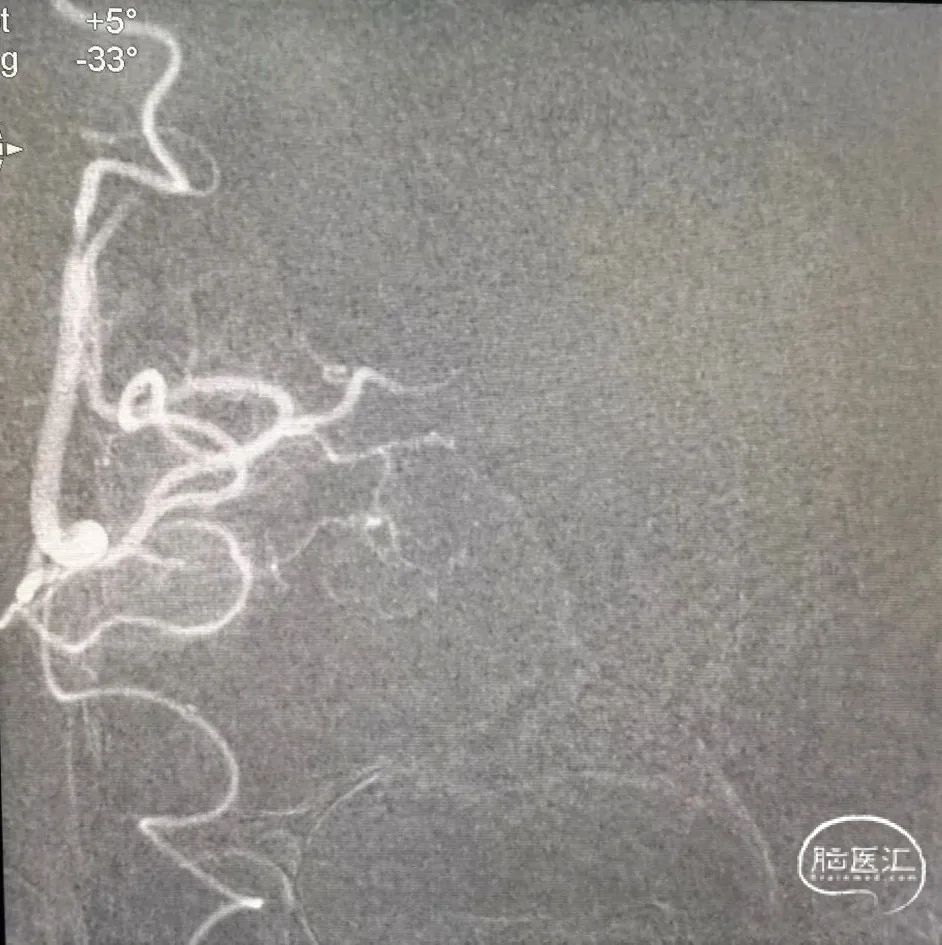

6F 115cm中间导管抽吸血栓2次后路图,见大脑中动脉、大脑前动脉闭塞。

大脑中动脉远端血管超选。

大脑前动脉第一次取栓后路图,血管仍闭塞,且长鞘掉到颈总。

再次超选发现颈内动脉起始部重度狭窄伴夹层。